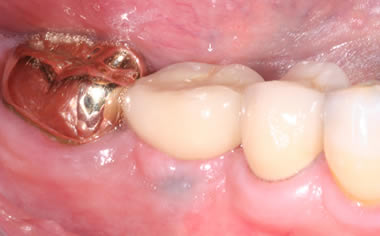

More back teeth replaced by dental implants

Case Four (4 images)